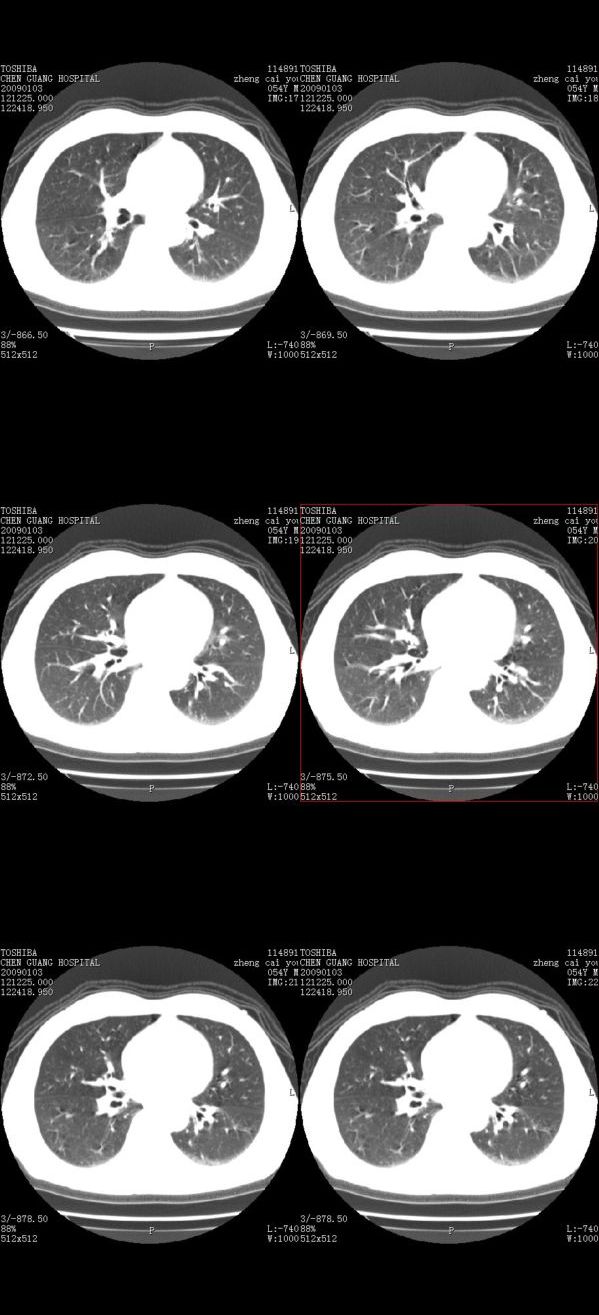

男,54岁,平时有吸烟后咳嗽、咯痰史,因右侧胸部(腋窝下)疼痛来检查平片,见右下肺动脉干起始处处结节,后到同学处做了平扫及增强。请各位老师帮忙看一下,不甚感谢!!!!!

肺窗薄扫、常规扫描均未见明确病变;右下肺门圆形与肺血管等密度影,考虑为血管变异;应该要纵隔窗才能进一步明辨。

x线表现与ct扫描相吻合。

主要应该看一下纵隔窗,感觉到右肺门的血管有局限性的扩张,呈结节状,再做个增强ct扫描.

右肺上叶前后段支气管夹角处可见一结节影,图像资料不全,不好下结论。